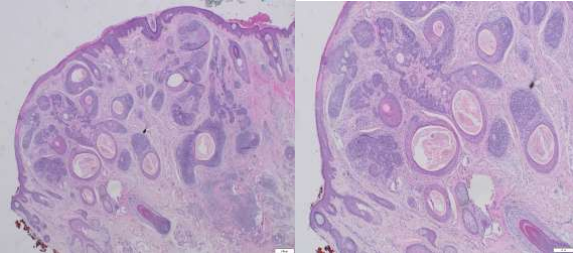

A 39-year-old male presented to the dermatology clinic of a Veterans Affairs medical center with a cystic nodule of the left medial eyebrow measuring 0.8 x 0.7 cm (figure 1). The patient was known to have CCS. His father, paternal aunt, and paternal grandfather had been diagnosed with Brooke-Spiegler syndrome (diagram 1). After presenting with multiple trichoepitheliomas, he had tested positive for a heterozygous pathogenic variant (c.2288-2289del p.Phe 763) of CYLD NM-015247.2CYLD. With this history, the clinical differential for this eyebrow lesion was cylindroma versus spiradenoma. Microscopic examination of the excision specimen revealed a well-circumscribed, dermal-based adnexal proliferation with areas recapitulating each part of the normal hair follicle: the?infundibulum, inner root sheath, outer root sheath, matrix, and bulb (figure 2.A&B). Areas resembling the infundibular portion of the hair follicle contained cystic cell aggregates lined by stratified squamous epithelium with a granular layer and filled with “basket-weave” orthokeratin (figure 2.C). Areas resembling the suprabulbar portion of the hair follicle showed clear cells as seen in the external root sheath and eosinophilic cells as seen in the internal root sheath (figure 2.D&E). Areas resembling the bulbar portion of the hair follicle showed immature basaloid cells and papillary mesenchymal bodies (figure 2.F&G). The lesion was uniformly circumscribed and without cytologic atypia, so a diagnosis of PF was rendered.

Figure 2.A&B Dermal-based adnexal proliferation of cystic and solid structures with follicular differentiation towards all components of the hair follicles (4X, 10X)

Figure 2.C Infundibular/isthmus differentiation (20x)

Figure 2.D&E Area resembling the suprabulbar portion of the hair follicle (20x)

Figure 2. F&G Area resembling bulbar areas with immature basaloid cells and papillary mesenchymal bodies